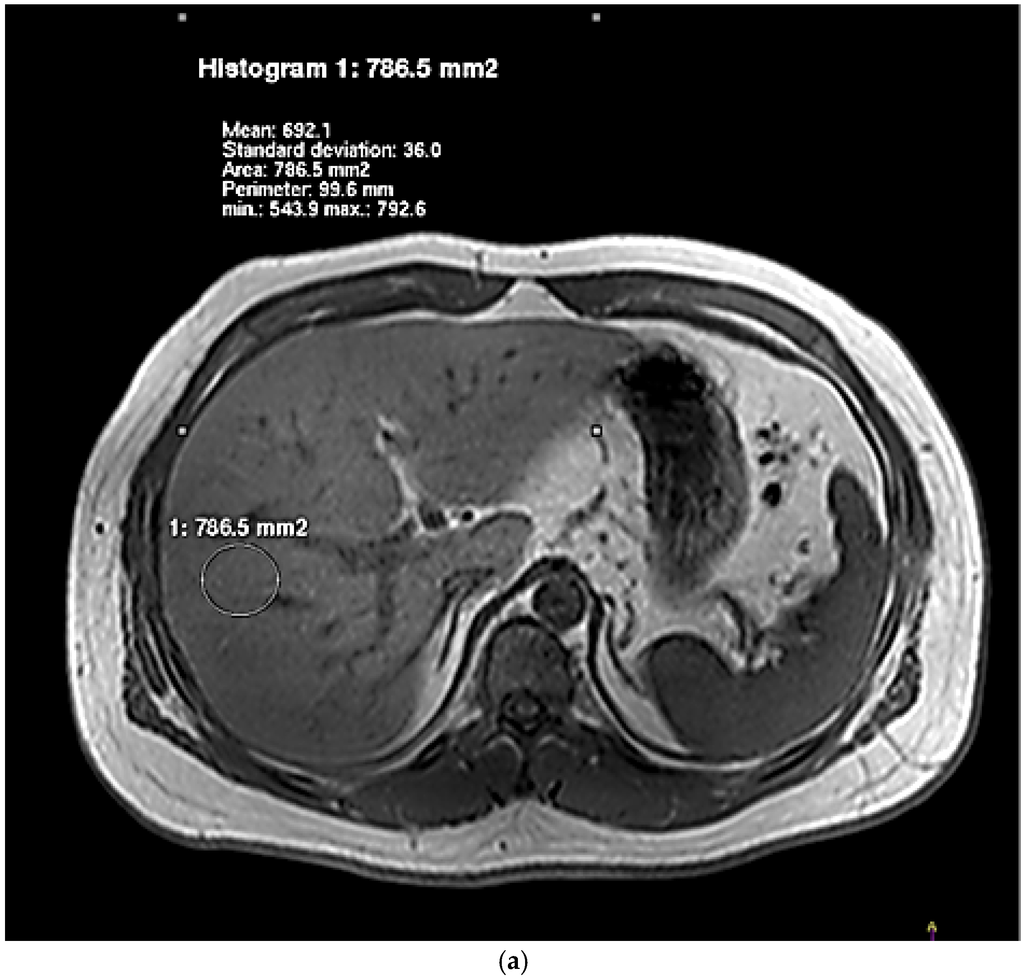

The degree of hepatic lipid contents assessed by IHL and HFF is presented in Table 2. For the examination by dual-echo MRI, the fat and water signals within a voxel were, respectively, additive and subtractive in the in-phase image and the opposed-phase image (Figure 1). In the images of NAFLD patients, there was a decrease of the signal intensity from the in-phase to an opposed-phase image. NAFLD patients showed significantly higher HFF than controls. Figure 2 showed typical examples of 1H spectra for a NAFLD patient (A) and a control subject (B). NAFLD group had higher IHL, which contrasted sharply with controls.

Figure 1.

Representative IP (a,c) and OP (b,d) images of livers obtained by using dual-echo sequence. Images of a NAFLD patient and a healthy individual were, respectively, Figure 1a–d.